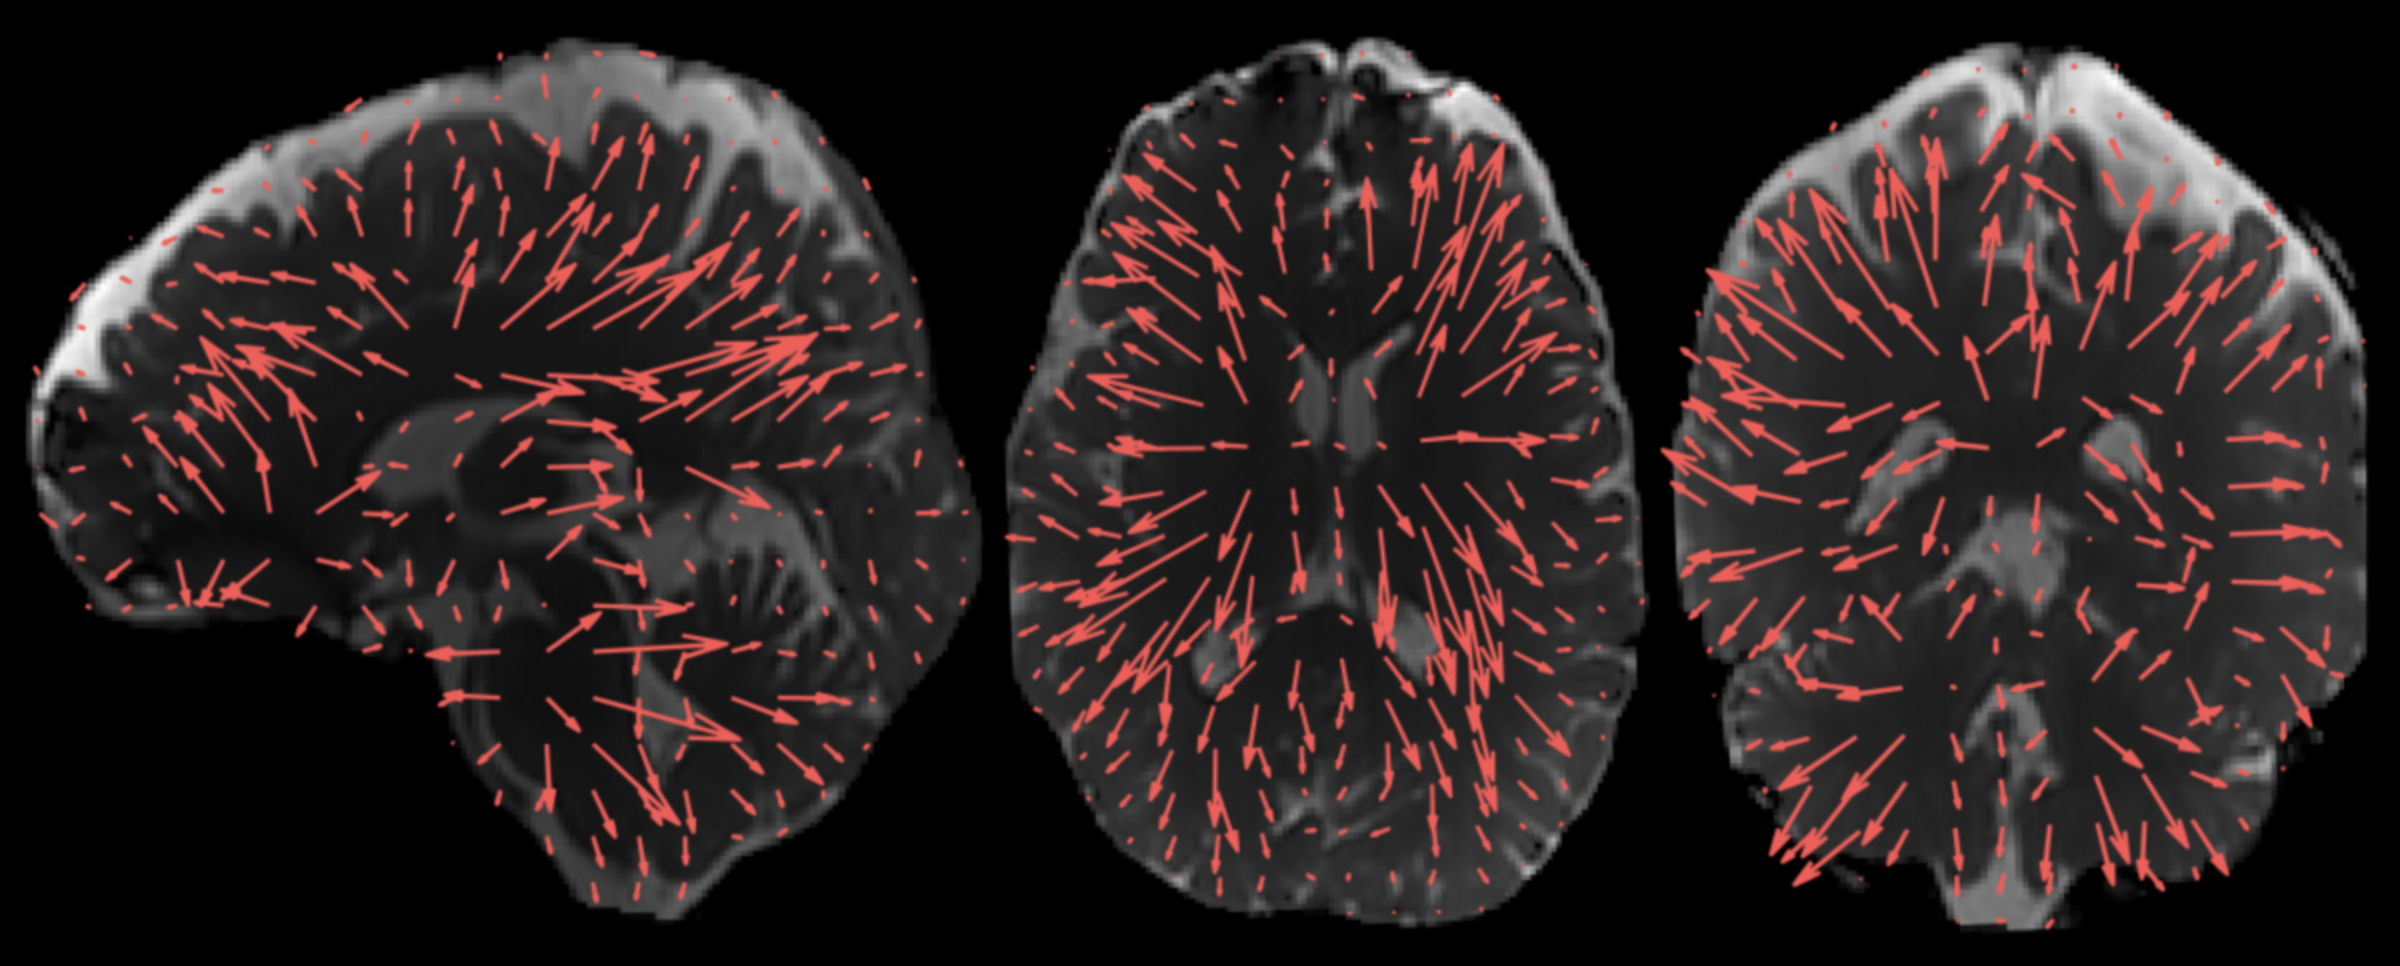

The 3D aMRI method, showing exquisite brain motion that is captured in all three planes of the brain (coronal, axial and sagittal views). Previously amplified motion was only reliably visible in the sagittal plane – the 3D aMRI method now captures motion in all planes. Outlined in Terem et al. Magnetic Resonance in Medicine (2021); Abderezaei et al. Brain Multi-physics (2021). https://youtu.be/bC05R_tcyW4

The arrows show the direction and amplitude of the brain’s movement. These displacement patterns, which were enabled by extra processing of 3D aMRI, may help us understand how the brain moves with different disorders. 3D aMRI method outlined in Abderezaei et al. Brain Multiphysics (2021); Terem et al. Magnetic Resonance in Medicine (2021).